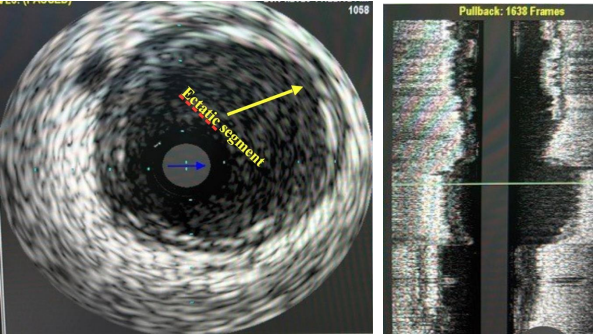

A Penumbra aspiration catheter was used, and after multiple passes, all the thrombus was aspirated (Figure 5). Due to the size mismatch and the fact that there was no dissection, only balloon angioplasty was performed and no stent was deployed. A repeat coronary angiography (Figure 6) and IVUS image (Figure 7) demonstrated no haziness with no evidence of distal embolization.

Figure 6: Coronary angiography post thrombectomy with complete resolution of thrombus. An ectatic segment is clearly visible.

Figure 7: Post thrombectomy IVUS image showing ectatic segment (arrow) with absence of thrombus